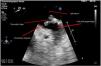

Patient admitted to the ICU due to SARS-CoV-2-induced pneumonia who required mechanical ventilation and was transferred to one of the hospital conventional wards after 14 days at the ICU treated with anticoagulant therapy with enoxaparin. He was readmitted due to respiratory failure. The CAT scan performed revealed the presence of thrombi in segmental arteries of both the right superior and left inferior lobes. The transesophageal echocardiogram performed revealed the presence of dense, spontaneous echocontrast in the right chambers (Appendix B; video 1 and Fig. 1). After the new hospital discharge, the patient showed low level of consciousness. The cranial CAT scan performed revealed the presence of an infarction at right medial cerebral artery level while the transesophageal echocardiogram performed revealed the presence of a coumadin ridge (variant of normality) with attached thrombotic material (Appendix B; video 2 and Fig. 2), and lack of cardiac shunt (Appendix B; video 3). A sequela of left residual hemiparesis remained at the ICU discharge. This is a clear example that the infection due to COVID-19 increases the risk of thromboembolic events.